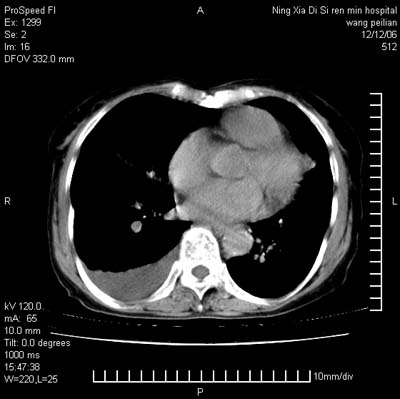

标题: CT5609:胸部:女77 病史不详 [打印本页]

标题: CT5609:胸部:女77 病史不详

两肺可见多个大小不等的结节,左侧有胸水,纵隔淋巴结增大,考虑是细支气管肺泡癌

两肺尖纤维索状影,两下肺结节块状影,且有钙化灶,右胸腔积液。考虑肺结核并胸膜炎。

两肺尖纤维索状影,两下肺结节块状影,且有钙化灶,右胸腔积液。考虑肺结核并胸膜炎肺间质纤维化

考虑:1、慢性支气管炎合并全小叶型肺气肿、间质纤维化;

2、双肺结核;

3、右侧胸膜炎(积液)。

1、双肺继发型肺结核(以纤维、增殖灶为主);

2、右侧胸腔积液;

3、其余符合老年肺改变。

双肺见多个结节状及条索状影,双侧胸腔积液,右侧叶间积液,考虑结核性胸膜炎